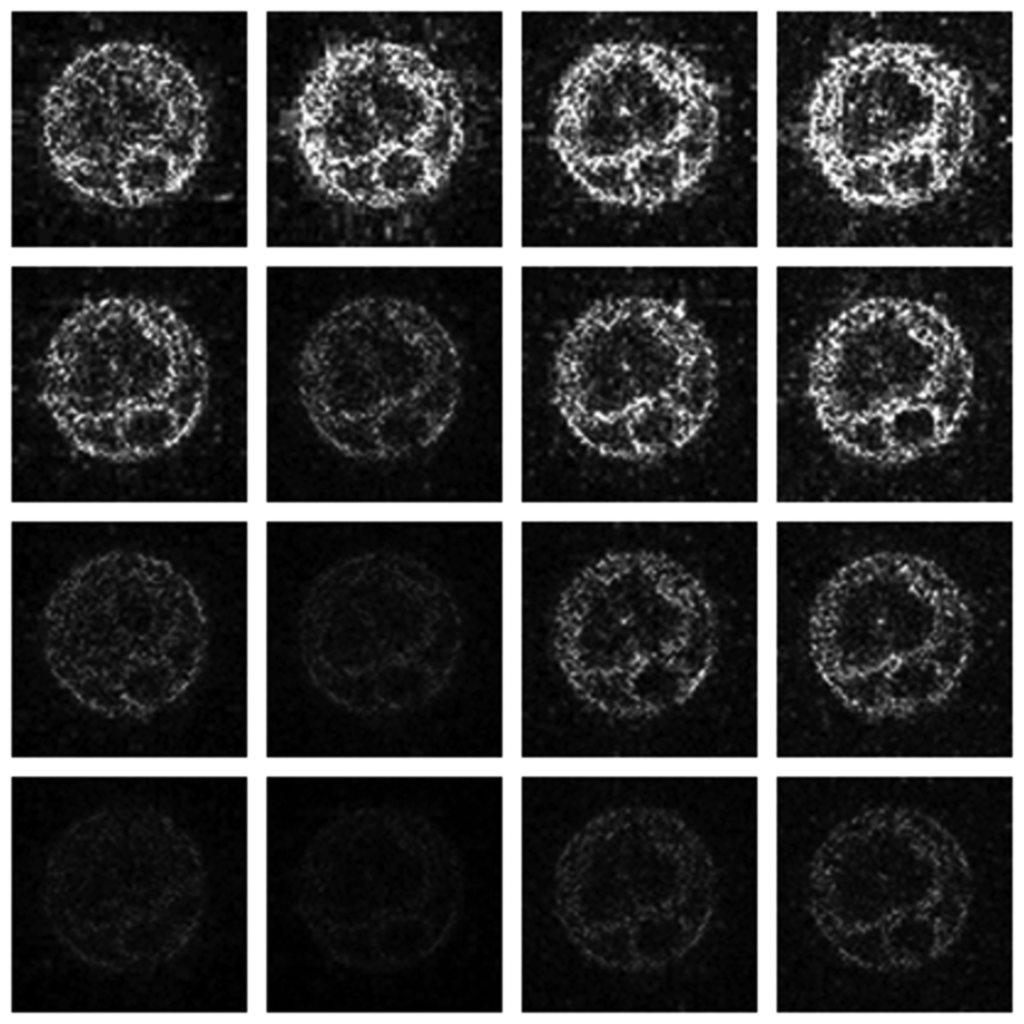

3.2. Qualitative Results

Numerical results do not always provide information about the qualitative nature of reconstruction. Thus, we provide reconstructed and difference images for visual inspection. Owing to limitations in space, we only show the results for 64 lines (this corresponds to a sampling ratio of 25%). Echo numbers 1, 5, 9 and 13 are shown in the following figures. In Figures 1 and 2, the ex vivo and in vivo reconstructed images are shown. In Figures 3 and 4, the difference images corresponding to ex vivo and in vivo imaging are shown respectively.

Looking closely at these figures, especially at the edges, one can see that the reconstruction quality progressively improves as one move from top to bottom. The worst results are obtained when the same Fourier map is used for all the echoes and simple row-sparse MMV recovery is used. The results improve slightly when rank-deficiency is introduced, but the improvement is only slight because the condition of incoherence is not satisfied when the same Fourier map is used for all the echoes. When different Fourier maps are used for the different echoes, the results from both group-sparse recovery and rank-deficient group-sparse recovery show improvement in the reconstruction quality; this is because of the better incoherence in the measurement operator. However, the best results are obtained when rank-deficient group-sparse recovery is used with different Fourier maps for different echoes.